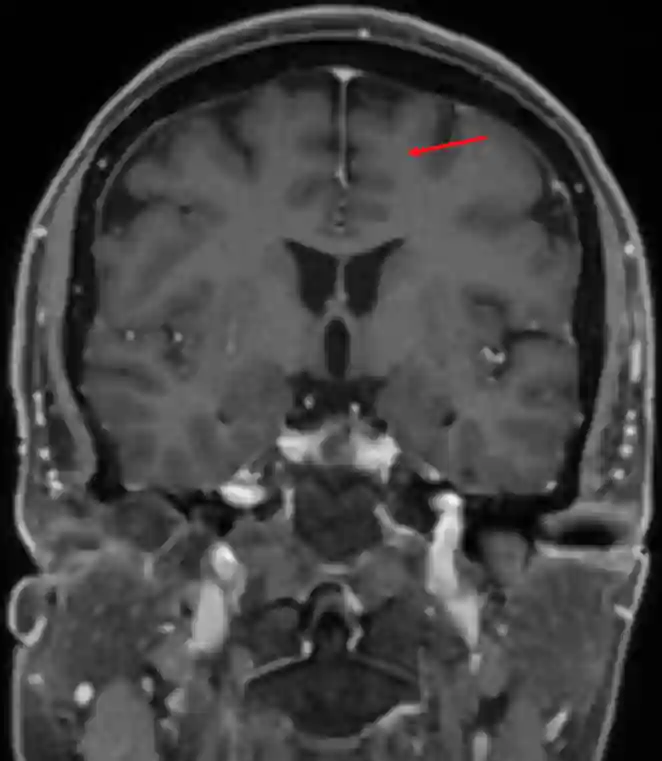

Gyrus frontalis superior im coronalen MRI Bild